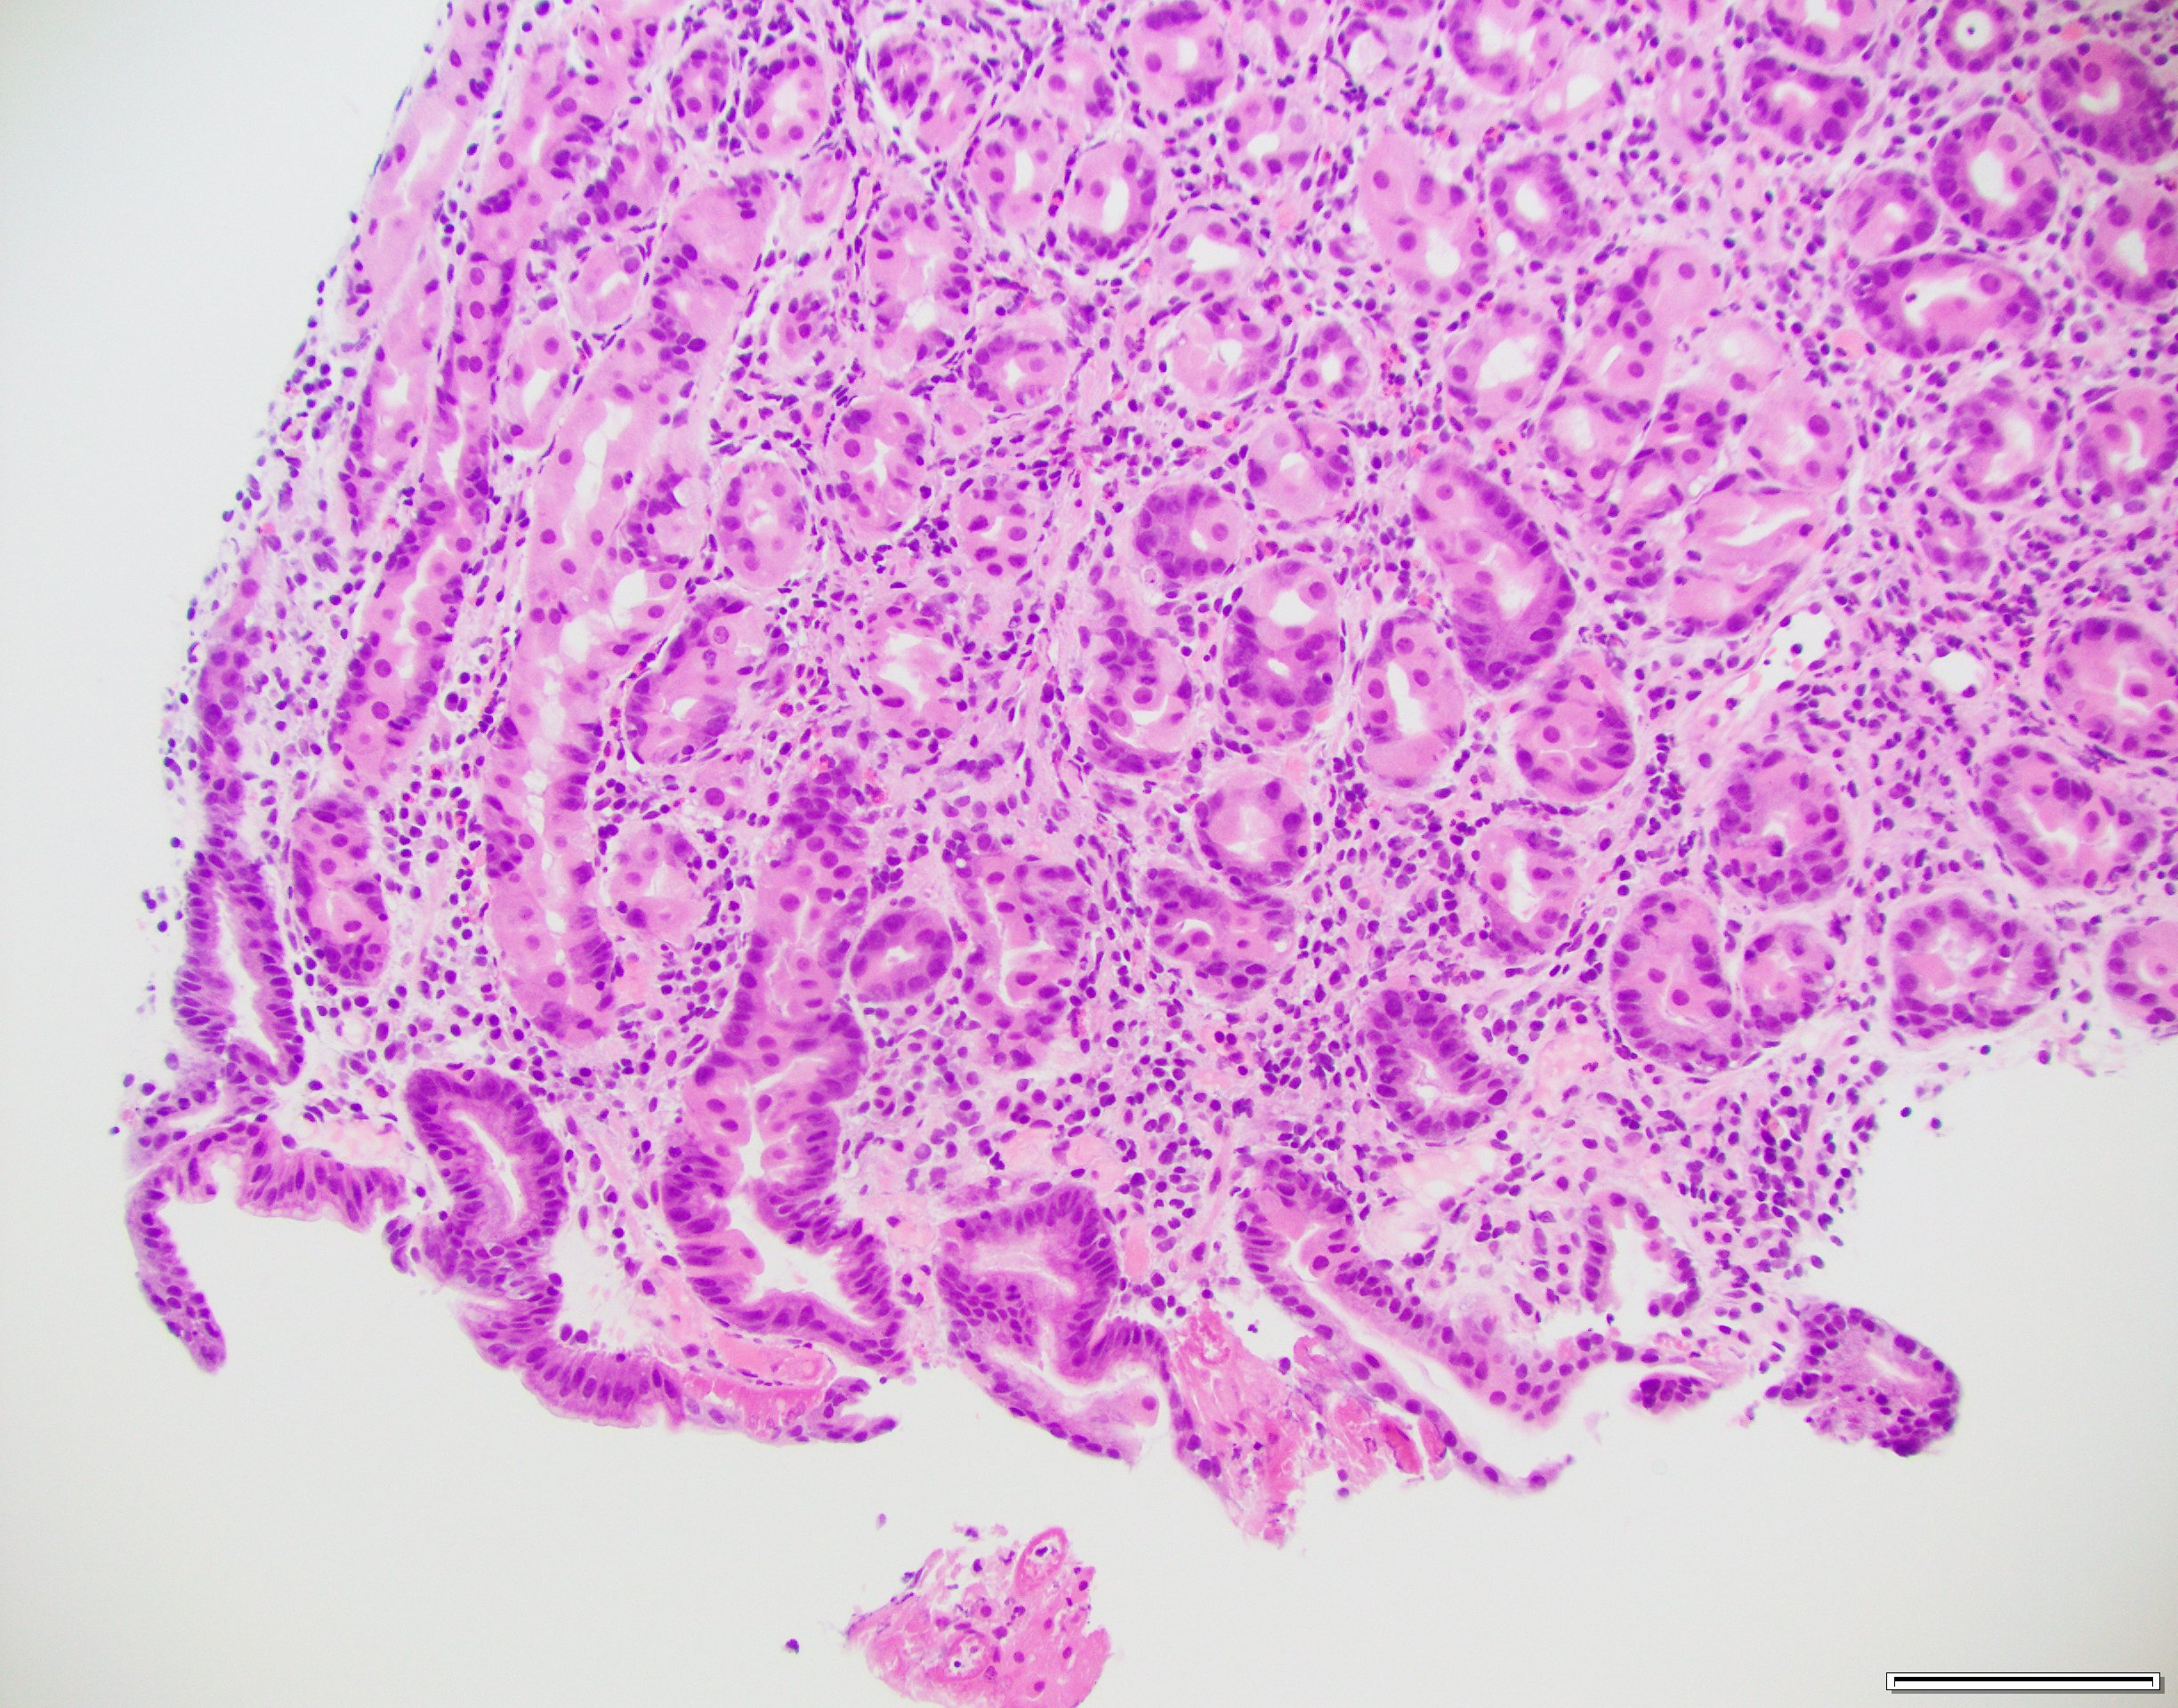

Case History

Gastric biopsy in an 80-year-old female.

What is the best diagnosis?

- H. pylori gastritis

- Autoimmune gastritis

- Iron-pill gastritis

- Doxycycline-associated gastritis

Answer: This biopsy shows eosinophilic necrosis of the superficial capillaries and capillary microthrombi. These histologic features are characteristically described with doxycycline-related gastric mucosal injury. H. pylori immunostain was negative.

Case contributed by: Deepti Dhall, M.D., Professor & Associate Director, Anatomic Pathology, GI Section Head